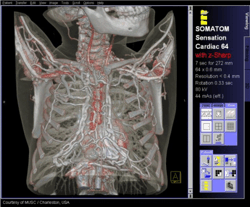

Снимки, созданные компьютерным томографом

А компьютерный томограф позволяет получить четкое изображение определенного среза тела. Сделав же "фотографии" нескольких таких срезов с шагом, скажем, в 1 миллиметр, мы получим очень качественное объемное, трехмерное изображение, которое позволяет увидеть в подробностях топографию органов пациента, локализацию, протяженность и характер очагов заболеваний, их взаимосвязь с окружающими тканями. Кроме того, чувствительность компьютерных томографов на порядок выше, чем обычных рентгеновских аппаратов: на рентгеновском снимке можно достаточно четко различить ткани, отличающиеся по степени поглощения рентгеновских лучей на 10-20%, а у современных компьютерных томографов этот показатель составляет 1-2%.

Реконструкция структуры тела на основе снимков компьютерного томографа:

В спиральной томографии тело виртуально «нарезается» не ломтиками, а «серпантином». Т.е. излучатель движется вокруг пациента по спирали. При этом за несколько секунд можно получить информацию о послойной структуре определенного участка тела. На основе данной методики появилась компьютерная ангиография, позволяющая эффективно выявлять патологию сосудов, 3D-рентгенография (объемная рентгенография) и даже виртуальная эндоскопия. При дальнейшем улучшении качества детекторов рентгеновского излучения и совершенствования компьютерной техники не исключена возможность появления в ближайшем будущем виртуальной биопсии, ведь с помощью рентгеновского излучения можно определять структуру вещества даже на молекулярном уровне.